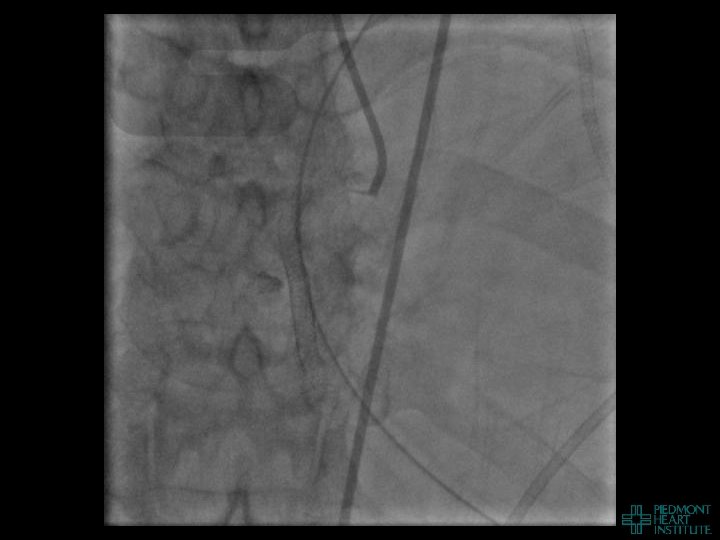

Coronary Perforation Methods of Patient Management • Dual Catheter (‘Ping Pong’) Technique • Prolonged

Coronary Perforation Methods of Patient Management • Dual Catheter (‘Ping Pong’) Technique • Prolonged balloon inflation and covered stents • Reversal of anticoagulation — Know contradictions to protamine sulfate for UFH; Avoid bivalirudin, LMWH — Reserve GP 2 b 3 a inhibition until successful crossing and wire change-out Embolization • — Coil, gelfoam, methacrylate, autologous blood/fat • Microcatheter Occlusion • Confirmation of successful management — Contralateral injection — Right heart catheterization — Echocardiogram — Contrast echocardiography